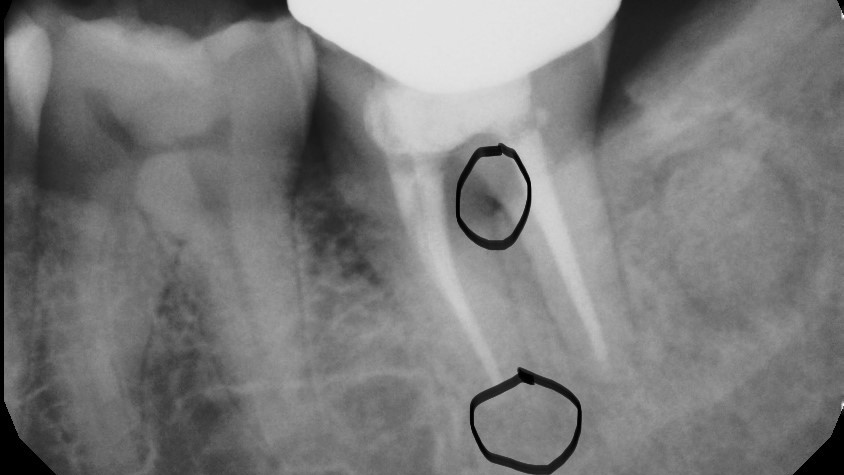

Root fracture is a common source of pain after root canal treatment and is of particular concern since it may be hard to diagnose (figure 1).5 Although new technologies such as three-dimensional imaging and microscopes have increased diagnostic ability, vertical fractures can still be hard to ascertain. Isolated periodontal pockets and a history of sharp pain that progresses to a dull throbbing pain upon mastication/palpation are common signs of fracture. Other common risk factors for fracture include: the lower second molar (most likely tooth to fracture), parafunctional habits including clenching/bruxism, large amalgam restorations, thermal injury, psychological stress, teeth with existing erosion, abrasion, and/or abfraction. A fractured tooth may need to be extracted to alleviate symptoms of pain (figure 2).

The periodontium surrounding the tooth can be a source of pain, especially if there is a concurrent periodontal lesion along with an endodontic lesion (figure 3). The tooth should be clinically examined and radiographs taken following root canal treatment to evaluate both hard and soft tissue. Hard-tissue defects, such as intrabony defects and furcation involvement, can cause inflammation leading to tooth pain. In addition, soft-tissue recession can expose root surfaces, which can then lead to sensitivity and tooth pain. Food impaction, especially if the tooth is temporized, can also mimic tooth pain. Gingival irritation from the rubber dam clamp used during the root canal can simulate tooth pain, but it is usually temporary and can be alleviated with rinses or medicaments. Referral to a periodontist may be required for pain of periodontal origin.